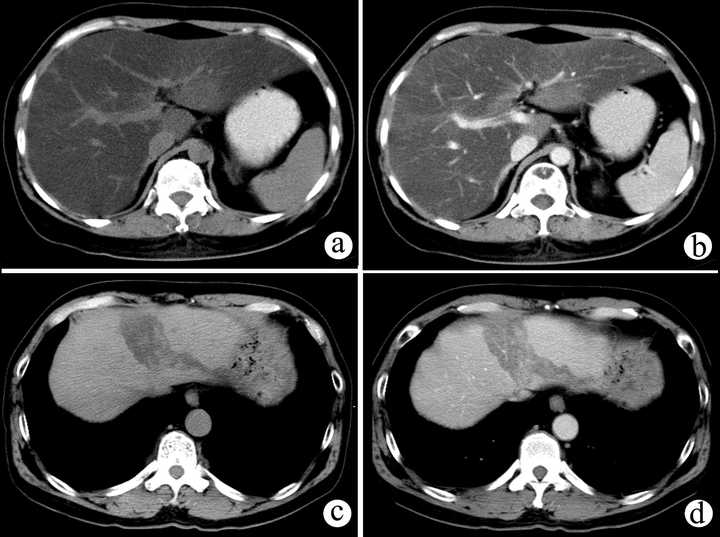

一般的CT图就长上面的样子,上面的图大概就是在腰或者胸附近切的几刀(= =我也不知是哪,专业人士轻喷)虽然真的CT图会有更多信息,但其实就把它当灰度图看就好了,CT值和器官密度什么的在这个项目就不管了。

一般的CT图就长上面的样子,上面的图大概就是在腰或者胸附近切的几刀(= =我也不知是哪,专业人士轻喷)虽然真的CT图会有更多信息,但其实就把它当灰度图看就好了,CT值和器官密度什么的在这个项目就不管了。